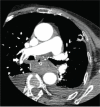

Fig. 3

Pulmonary embolism: Computed tomography image with pulmonary embolism protocol: filling defect (white arrow) within branches of the pulmonary artery supplying the upper part of the right lower lobe.